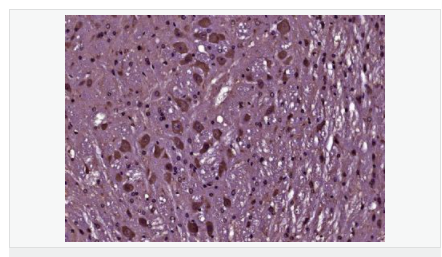

| 產品應用 | WB=1:500-2000 ELISA=1:5000-10000 IHC-P=1:100-500 IHC-F=1:100-500 Flow-Cyt=1μg/Test IF=1:100-500 (石蠟切片需做抗原修復) not yet tested in other applications. optimal dilutions/concentrations should be determined by the end user. |